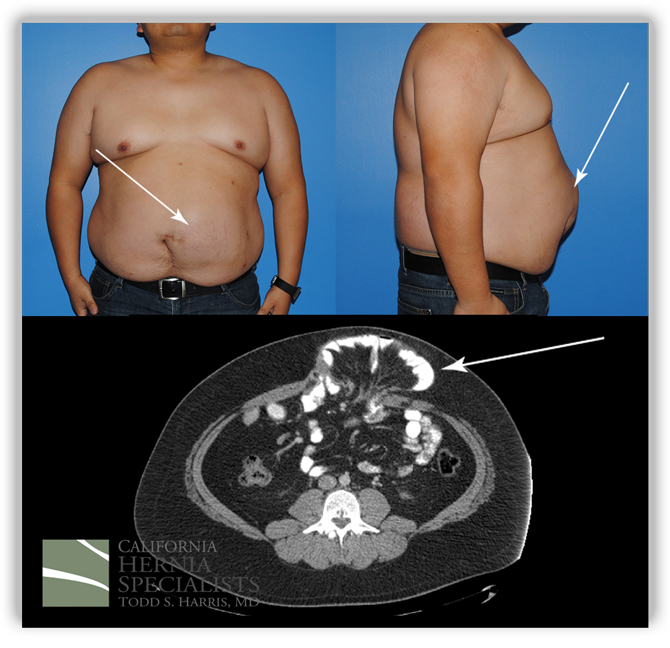

This patient had been operated on two previous times by an outside surgeon. The first surgery was done without mesh. After it recurred almost immediately, the same surgeon used a ‘large piece of mesh’ as was described by the patient and the operative report. Unfortunately shortly after this surgery, the bulge returned and the patient developed increasing pain.

The patient presented to California Hernia Specialists for a second opinion before returning for a third surgery. The patient underwent a physical exam and a CT scan to evaluate the size of the hernia. A number of options were presented to the patient and ultimately it was decided to treat him with an open recurrent umbilical hernia repair.

A ‘tummy tuck’ incision was used to help tighten and remove excess skin and the old scar. The old mesh had completely separated from the muscle and was stuck to the small intestines internally. Careful removal of the mesh was required to free the intestine from the hernia. The muscle was closed and a new piece of advanced mesh was placed under the muscle to reinforce the repair. The images below are from before and after his hernia surgery.

This image shows photos before his surgery along with the CT image corresponding to his hernia. The arrows point out the obvious hernia.